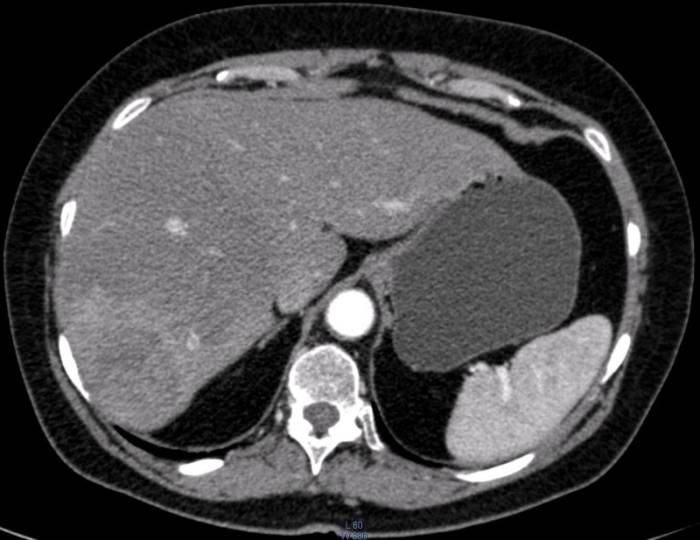

На КТ и МСКТ печени хорошо видны все части органа. Исследования помогают определить локализацию патологии по секторам и оценить состояние всех сегментов. Благодаря этому врачи могут поставить точный диагноз и назначить правильное лечение пациенту.

КТ с контрастом

Контрастирование обычно выполняется в две фазы — артериальную и портально-паренхиматозную.

Контраст вводится в вену, затем через определенный промежуток начинается сканирование. В артериальной фазе получается изображение кровеносных сосудов, контрастируются также опухоли с обширным сосудистым руслом.

- Кавернозная гемангиома в артериальной фазе накапливает контраст в виде пристеночного узла, насыщенность которых примерно равно плотности крови в аорте.

- Метастазы чаще всего усиливаются в виде периферического кольца. Рак накапливает контраст неравномерно, в больших опухолях обнаруживаются темные участки некроза и более светлые мягкотканные включения.

- Для диагностики фиброзных опухолей, например, фокальной нодулярной гиперплазии, добавляется отсроченная фаза.

Компьютерная томография

Также для изучения состояния печени используется КТ (метод компьютерной томографии). Он позволяет определить почти все серьезные морфологические изменения на раннем этапе их развития:

- Киста и поликистоз,

- Тромбоз и обструкция воротной вены,

- Гнойные образования,

- Жировая дистрофия,

- Цирроз печени,

- Онкологический процесс,

- Гепатит, лимфома.

Нормальный размер печени по продольной линии измерения — от 250 до 300 миллиметров. Высота левой доли должна составлять не более 150-160 миллиметров, высота правой — не более 200-220 миллиметров. Показатели, которые свидетельствуют о здоровом состоянии печени:

- Более высокая плотность полости печени, нежели полости прилегающих органов (желчного пузыря, поджелудочной железы или селезенки),

- Легко определяемые воротная вена, желчевыводящего протока и печеночной вены,

- В структуре печеночных долек не обнаруживаются артерия печени или желчевыводящий проток.